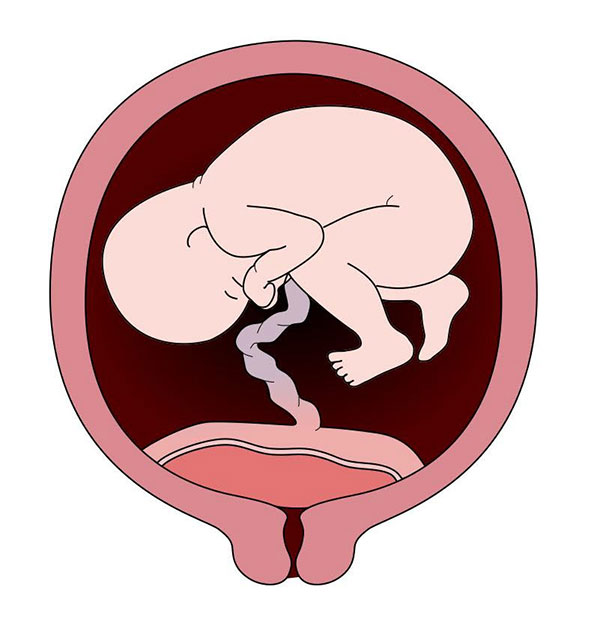

قیمت: 45٬000 تومان - دسته بندی فایل: پاورپوینتدانلود پاورپوینت بررسی انواع جفت سر راهی

خرید پاورپوینت حرفه ای با موضوع بررسی انواع جفت سر راهی با قیمت استثنایی از لوکس فایل